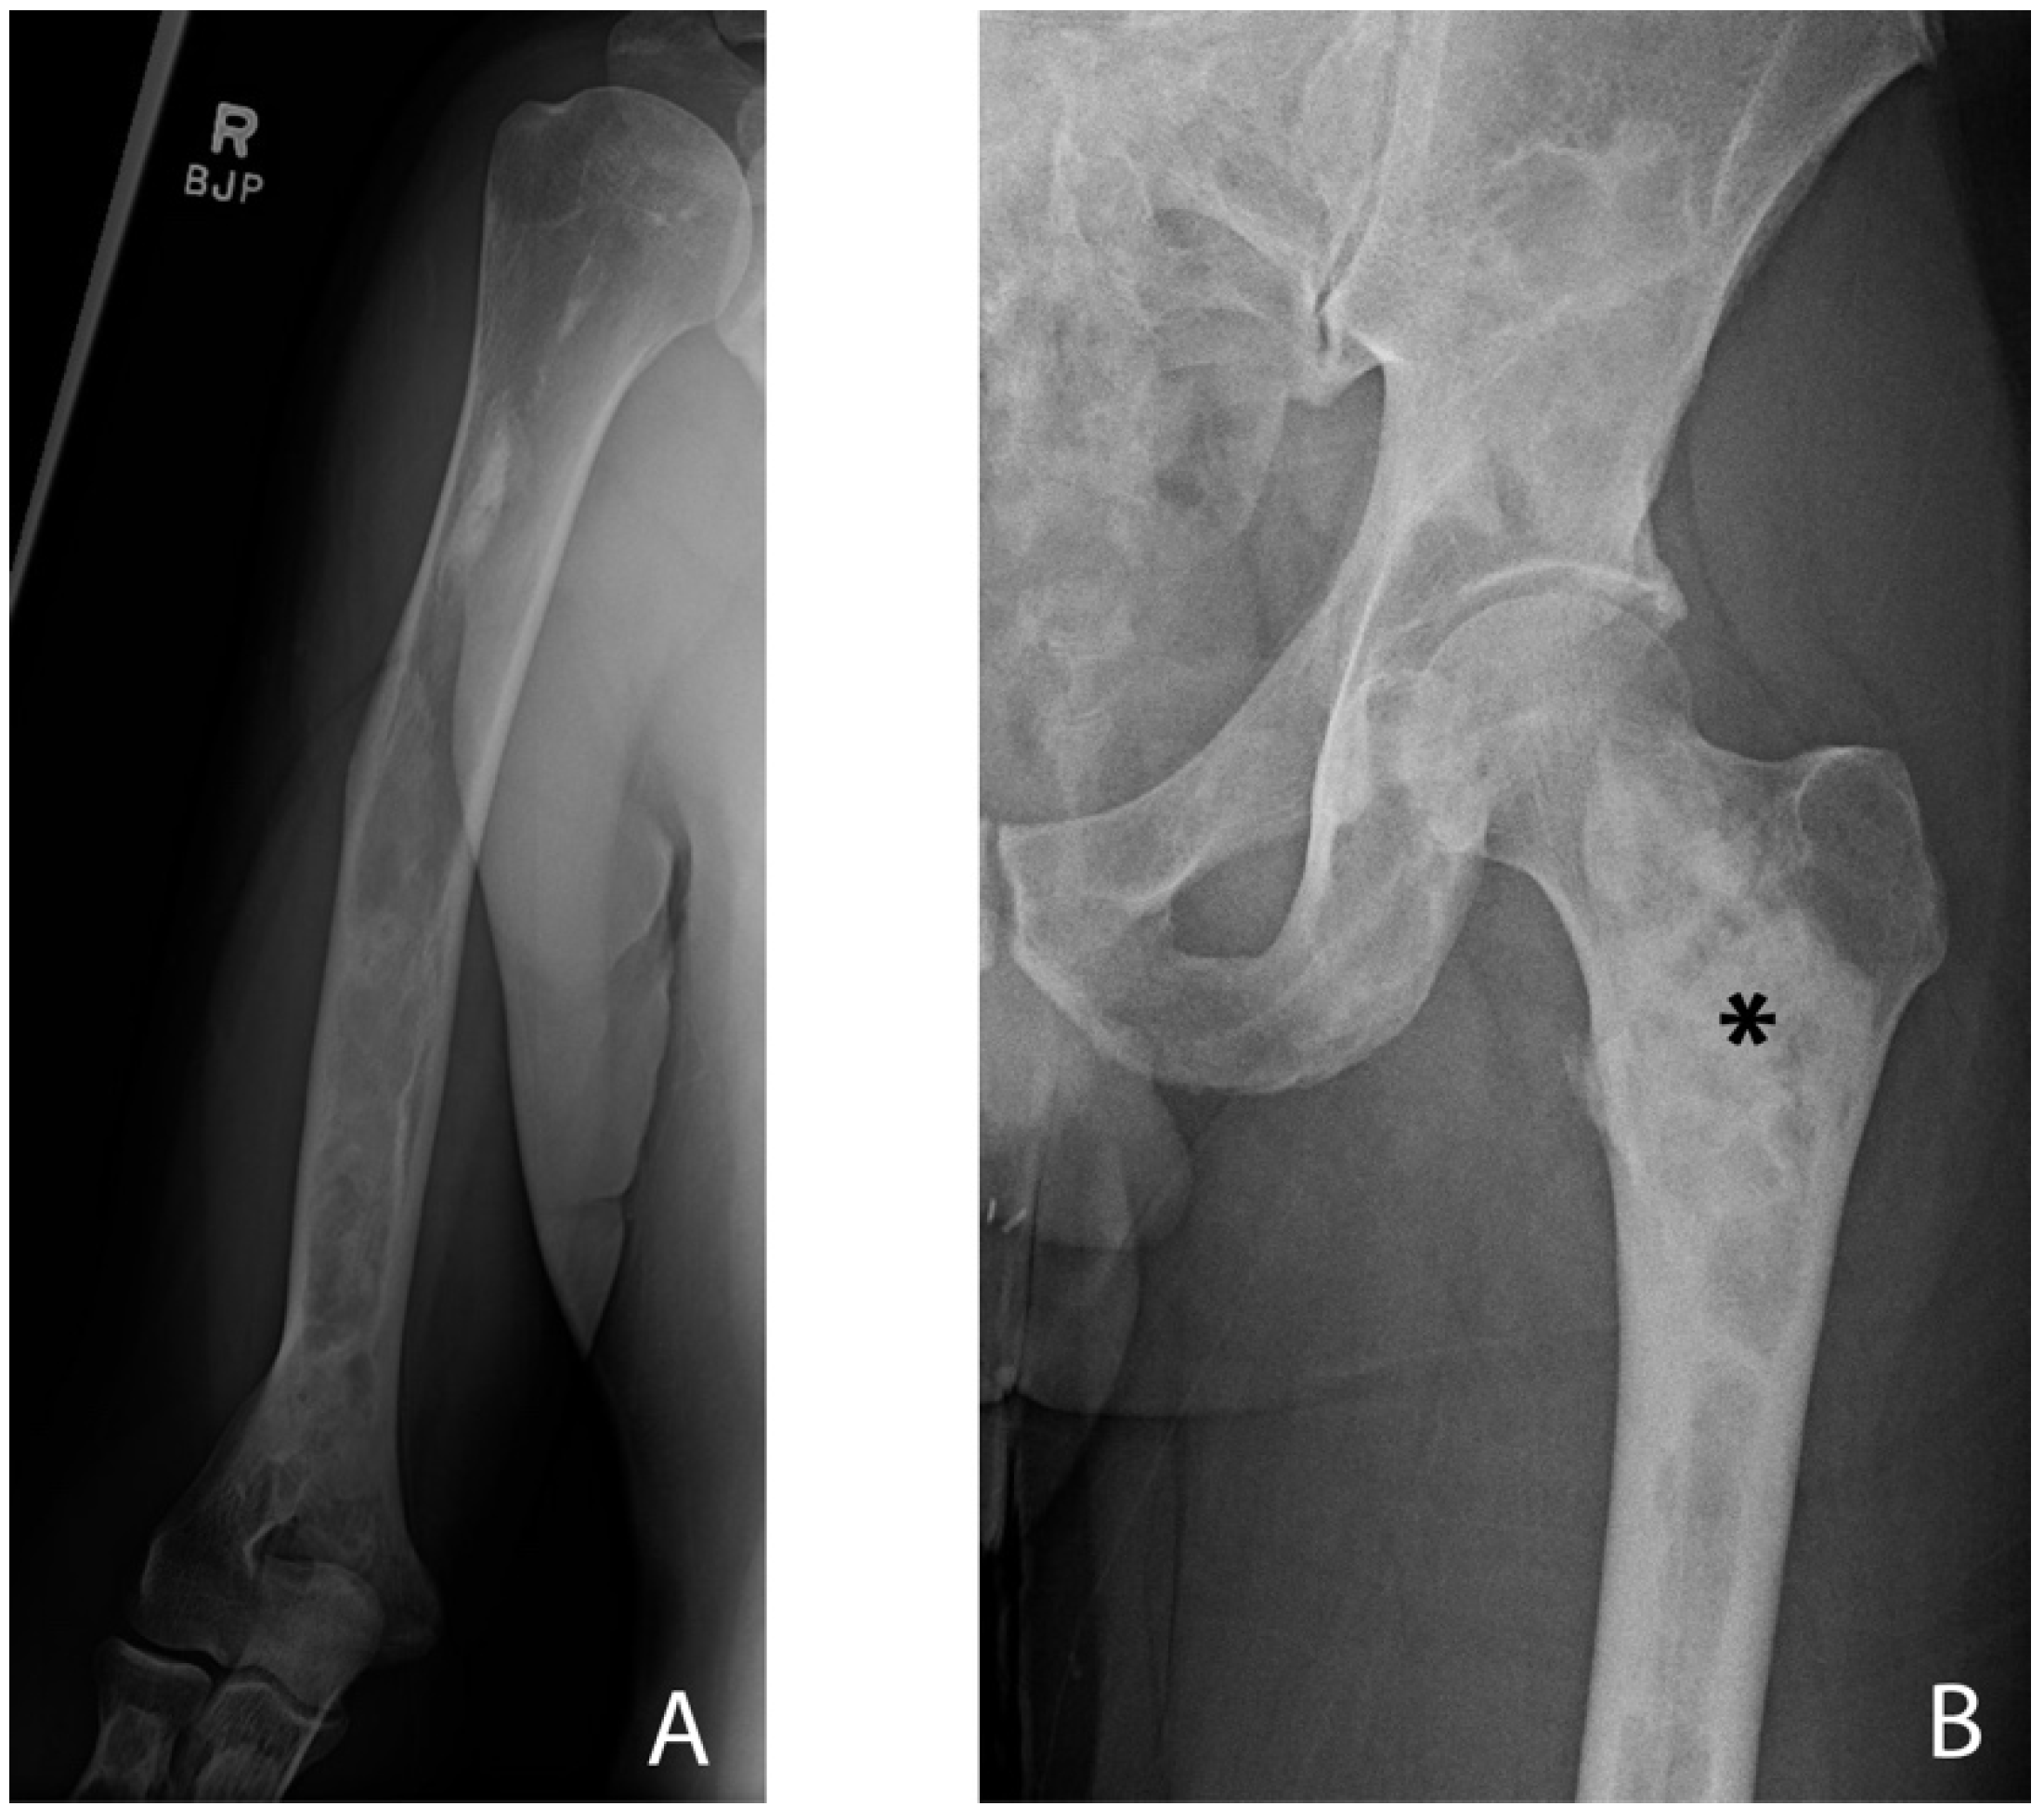

- Wang, Y.; Luo, Y.; Min, L.; Zhou, Y.; Wang, J.; Zhang, Y.; Lu, M.; Duan, H.; Tu, C. The West China Hospital radiographic classification for fibrous dysplasia in femur and adjacent bones: A retrospective analysis of 205 patients. Orthop. Surg. 2022, 14, 2096–2108. [Google Scholar] [CrossRef]

- Zhang, X.; Chen, C.; Duan, H.; Tu, C. Radiographic classification and treatment of fibrous dysplasia of the proximal femur: 227 femurs with a mean follow-up of 6 years. J. Orthop. Surg. Res. 2015, 10, 171. [Google Scholar] [CrossRef]

- Ippolito, E.; Farsetti, P.; Boyce, A.M.; Corsi, A.; De Maio, F.; Collins, M.T. Radiographic classification of coronal plane femoral deformities in polyostotic fibrous dysplasia. Clin. Orthop. Relat. Res. 2014, 472, 1558–1567. [Google Scholar] [CrossRef]